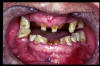

CM Caries, patología periodontal, desgaste.